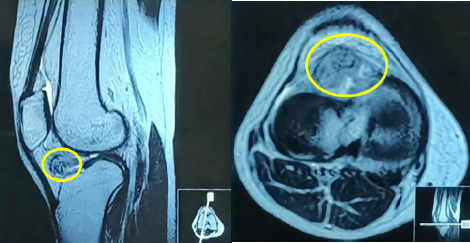

Tenosynovial giant cell tumor (GCT) is a rare, benign disorder involving the joint's synovial lining, tendon sheath or bursa. It can be classified as localized or diffuse based on its pattern and behavior. Localized form is extremely rare in knee joint. We present an unusual case of localized form of GCT in Hoffa's fat pad in a young female, treated with arthroscopic resection and monitored for over two years with no recurrence. Despite its rarity, GCT of Hoffa's fat pad should be considered in cases of non-traumatic knee pain.